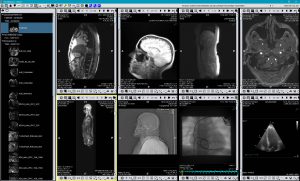

TM-PACS

Het maakt de compressie, beveiliging, opslag en visualisatie van radiologische beelden mogelijk met tools voor gerichte weergave en visualisatie (zoom, vergrootglas, annotaties, afstandmeting, opvolging van metingen, enz.). De gebruiker kan zo tegelijkertijd beelden van coronarografie, PET-beelden uit de nucleaire geneeskunde en meer klassiek beeldmateriaal (NRM, CT Scan, echographie, enz.) visualiseren. Het gebruik van onderzoeksgerelateerde labels maakt het mogelijk onderzoeksgroepen samen te stellen en die met één enkele klik te openen. Een gepersonaliseerd zoeksysteem maakt het mogelijk het patiëntdossier of het gewenste onderzoek zeer snel te vinden. Het beeldscherm is geoptimaliseerd zodat weergave op meerdere schermen mogelijk is. Hierbij mogen we ook de integratie van de RIS- en PACS-software die op dezelfde diagnosestations worden geïnstalleerd, niet vergeten.